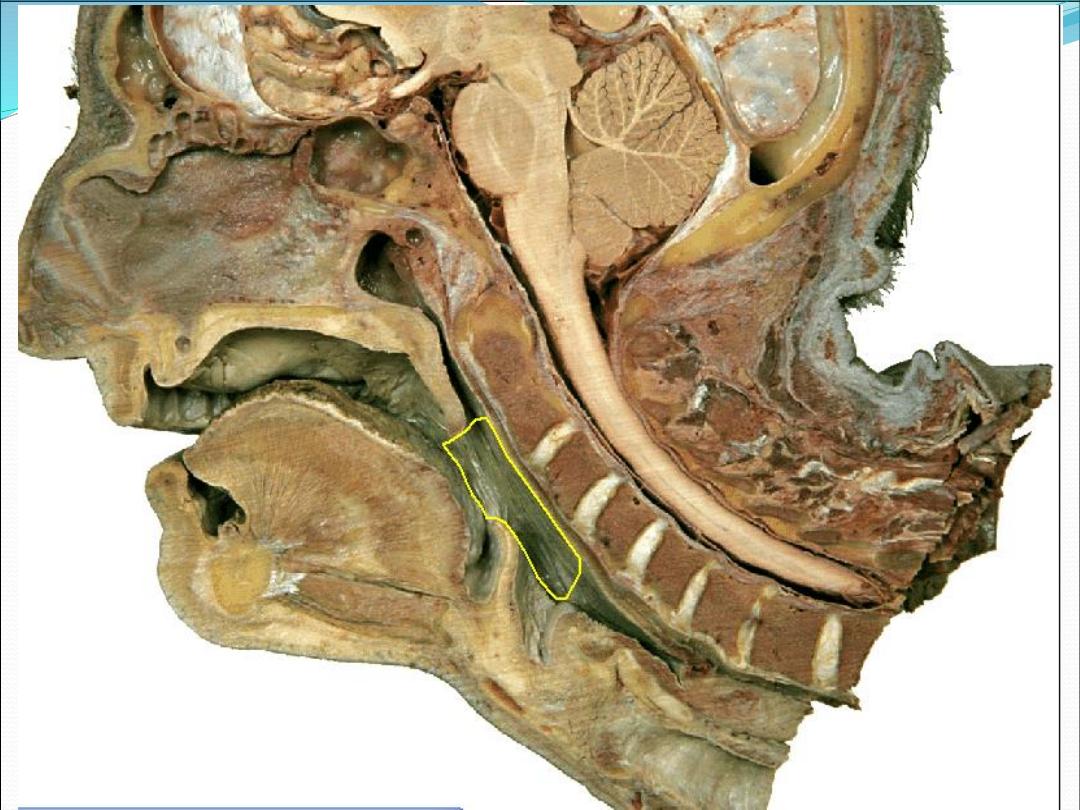

Pharynx

It is a muscular tube

Lies behind and communicates with the nasal, oral,

and laryngeal cavities

Lies in front of the prevetebral fascia

About (12 cm) in adult

Pharyngeal subdivisions

Nasopharynx

Oropharynx

Hypopharynx

Nasopharynx

Extend from the base of the skull to the level of soft

palate

Continuous with the nasal cavity througth the

Oropharynx

Extend from the junction of soft and hard palate to the

floor of the valleculae (level of hyoid bone)

Hypopharynx

Extend from the level of hyoid to the lower edge of the

cricoid